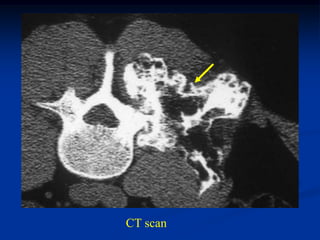

Case #587

42 year male with

combined periosteal

chondroma and

enchondroma next to

each other in femur

enchondroma

Bone scan

periosteal chondroma

Sagittal CT scan

Axial CT scan at level of enchondroma

periosteal

chondroma

CT scan